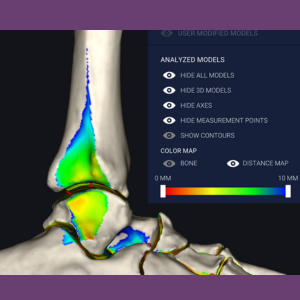

Advanced Visualization

Advanced visualization enhances the diagnostic capabilities of WBCT combined with sophisticated 3D techniques in Computer Science to offer new insights into bone and joint physiology and pathology. Techniques such as Artificial Intelligence (AI) and Machine Learning (ML) are utilized. The Grav-ET lab is equipped with Disior software (https://www.disior.com/), which provides the research team with segmentation and advanced visualization tools, including distance measurement, coverage mapping, and automated 3D measurements. Hounsfield Unit (HU) analysis allows the study of local variations in Bone Mineral Density (BMD), named after Sir Godfrey Hounsfield, Nobel Prize winner for the invention of CT.